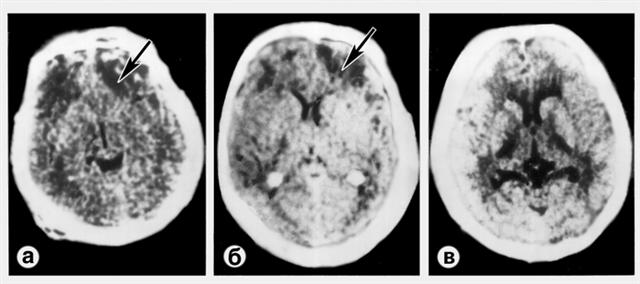

Рис. 1. Компьютерные томограммы при тяжелом ушибе левой лобной доли (а, б) и диффузном аксональном повреждении мозга (в): а — очаговое поражение мозга, проявляющееся неоднородным повышением плотности мозга (указано стрелкой); б — очаги интенсивного гомогенного повышения плотности в местах кровоизлияний в вещество мозга (крупный очаг указан стрелкой); в — отек и набухание мозга со сдавлением ликворных вместилищ и путей.